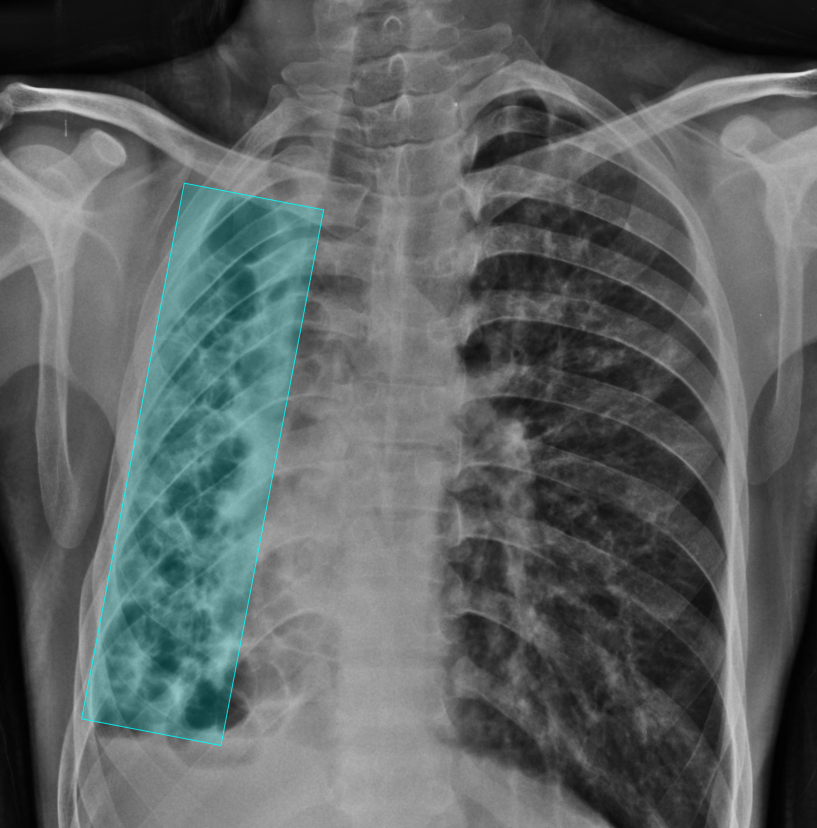

What does AI-detected pathology look like?

Eight examples of AI-annotated chest X-rays with color-coded pathology overlays

Chest X-ray with AI-detected Bronchiectasis highlighted

Bronchiectasis